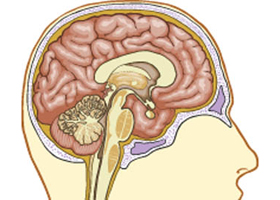

Az endokrinológia aktuális problémái

Esetismertetések

14.00 Érdekes endokrinológiai esetek